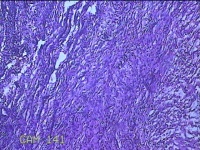

左侧卵巢囊肿⑴

性别

女

年龄

34岁

临床诊断

左侧卵巢子宫内膜异位囊肿

一般病史

下腹痛3小时入院。

标本名称

大体所见

灰白暗红色囊性肿物8x2.5x0.7cm一个,表面糜烂,部分已切开,囊内容物已流失,囊壁厚0.1cm。